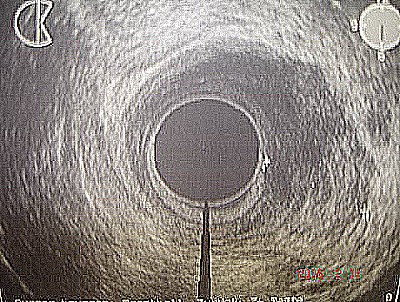

Abb. 10- 12: Exakte Darstellung des noch nicht fortgeschrittenen bösartigen Tumors des unteren Mastdarmes mit Verdrängung und noch nicht Überschreitung der eigentlichen Muskelschicht. Abb. 10- 12: Exakte Darstellung des noch nicht fortgeschrittenen bösartigen Tumors des unteren Mastdarmes mit Verdrängung und noch nicht Überschreitung der eigentlichen Muskelschicht.